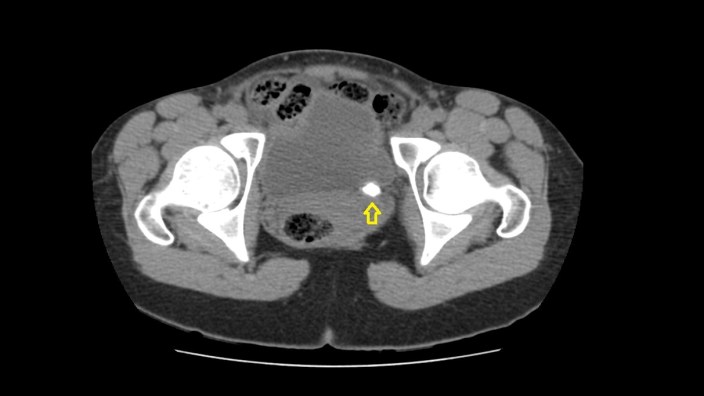

Cuando tu ves el estudio que te he enseñado, ¿Qué piensas?. Lo más normal es que pienses que el paciente, tiene una litiasis yuxtavesical izquierda, que observas en la placa simple de la imagen 2, corresponde con la imagen del TAC de Abdomen sin contraste, en la imagen 1. En el contexto de su patología, al paciente se le realiza una cistografía para valorar reflujo, que se demuestra en la imagen 3 y la imagen 4, donde puedes ver la existencia de reflujo en lado derecho, que tiñe el riñón derecho.

Finalmente, para hacerlo todo más verosímil, observas la ecografía donde ves cortes transversos y longitudinales donde ves una imagen hiperecogénica con una sombra posterior marcada, justo anclada la unión ureterovesical izquierda, al colocar el color en esa localización, podemos ver la típica imagen de artefacto de centelleo, que marca claramente la presencia de una litiasis en otros tanto estudios, imágenes 5 y 6.

Las flechas amarillas indican las regiones donde puedes encontrar la semiología que es la base del post de hoy.